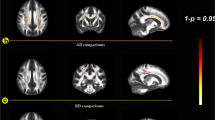

For each group, a whole-brain-voxel-based repeated-measures ANOVA model was applied to FA, using SPM8 (Ashburner and Friston 2011), with time as within-subject factor and verbal IQ and depression score as covariates-of-no-interest (Deprez et al. 2012). As before (Deprez et al. 2012), covariates (i.e. scanner upgrade and goodness of tensor-estimation-fit) were added to account for scanner drift, upgrades and maintenance (Harrison et al. 2011; Takao et al. 2012). From the repeated-measures ANOVA model we extracted adjusted mean FA values at all time points, in the four ROI previously associated with chemotherapy-related changes from t1 to t2 (Deprez et al. 2012) (Fig. 2): a region covering (1) the corona radiata and corpus callosum, (2) frontal (superior longitudinal fasciculus (SLF)), (3) parietal (SLF) and (4) occipital (forceps major) WM tracts. Post-hoc tests with Bonferroni correction were used to compare main effects between timepoints.

Longitudinal results in ROI. Mean FA values of patients that participated at the 3 timepoints in the 4 regions of interest. t1, assessment at baseline; t2, assessment 3–4 months and t3: 3–4 years after treatment. ROI1: region covering parietal part of corona radiata and corpus callosum; ROI2: region covering frontal part of superior longitudinal fasciculus; ROI3: region covering parietal part of superior longitudinal fasciculus; ROI4: region covering part of forceps major. * corrected p-value <0.05 ** corrected p-value <0.001

Two C+ patients were excluded from the analysis due to excessive motion and signal dropout in one of the DTI images. Repeated-measures ANOVA showed that mean FA values differed significantly between timepoints (ROI1: F = 7, p = 0.002; ROI2: F = 14.1, p < 0.0001; ROI3: F = 10.5, p < 0.0001; ROI4: F = 18, p < 0.0001). Post-hoc tests showed significant decreases from t1 to t2 followed by significant increases from t2 to t3 in FA (p < 0.02, corrected for 4 ROI) in the chemotherapy-treated group in the four ROIs (Fig. 2). No significant differences in FA values were seen for the group of healthy controls (ROI1: F = 0.9, p = 0.42; ROI2: F = 1.2, p = 0.30; ROI3: F = 1.7, p = 0.20; ROI4: F = 0.9, p = 0.40) and a significant group x time interaction was found in 3 of the 4 ROI (ROI1: F = 0.8, p = 0.45, ROI2: F = 6.5, p = 0.004, ROI3: F = 3.9, p = 0.029; ROI4: F = 5.6, p = 0.008).